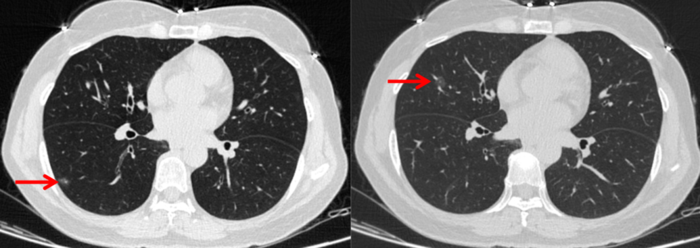

多发性的肺结节指的是两个或更多≤3cm的肺部类圆形阴影,其中长的最大我们一般叫他主病灶,其他的就是次病灶。对于多发肺结节评估一般比较复杂,我们一般要每个结节都仔细的进行评估检查,现在的研究提示多个肺结节大多是多原发的,也就是指每个肺结节相互独立的产生,但是也有很少一部分是肺内转移形成的。